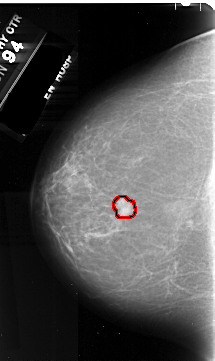

FILE: A_1055_1.LEFT_MLO.OVERLAY

TOTAL_ABNORMALITIES 1

ABNORMALITY 1

LESION_TYPE MASS SHAPE IRREGULAR MARGINS SPICULATED

ASSESSMENT 5

SUBTLETY 5

PATHOLOGY MALIGNANT

TOTAL_OUTLINES 1

BOUNDARY